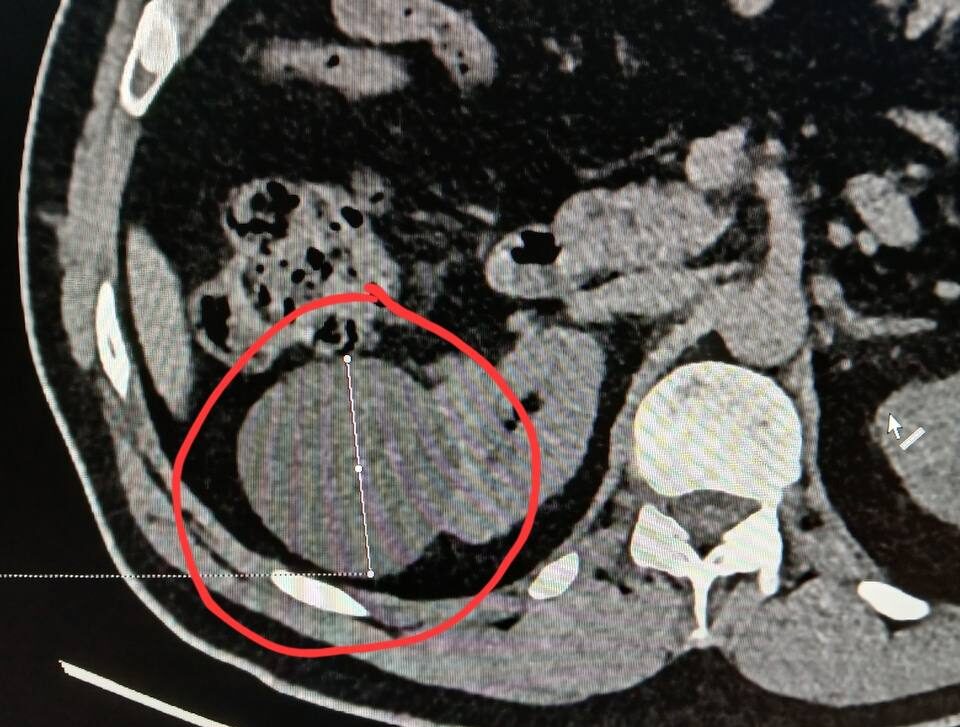

«Киста почки при компьютерной томографии визуализируется как объёмное жидкостное образование округлой формы с чёткими ровными контурами. Ключевым диагностическим критерием является характеристика её содержимого и поведение при контрастном усилении», — рассказал Михаил Охлопков.

Сложные кисты требуют, по его словам, особого внимания. Наличие перегородок, утолщение стенок, кальцинаты могут привести к онкологии. Поэтому такие кисты могут потребовать хирургического вмешательства.